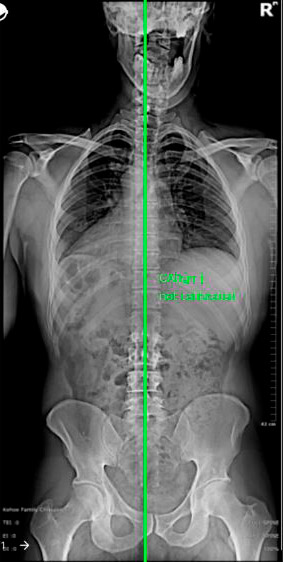

No plano coronal, o eixo vertebral deve coincidir com o ponto médio do sacro. Até 3cm de deslocamento é aceitável (equilíbrio compensado) Fig. 2.

Fig. 2 – Equilíbrio coronal